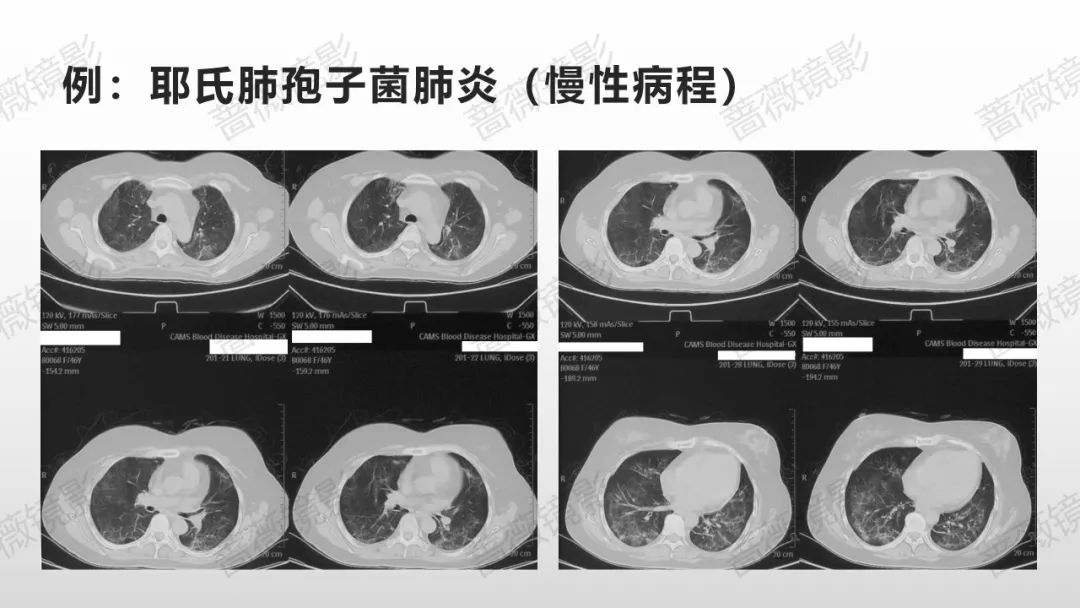

我对支气管肺泡灌洗液mNGS病原学检出的深层思考

虚拟导航引导超细内镜精准加压BAL能够解决什么问题?其短板如何弥补?